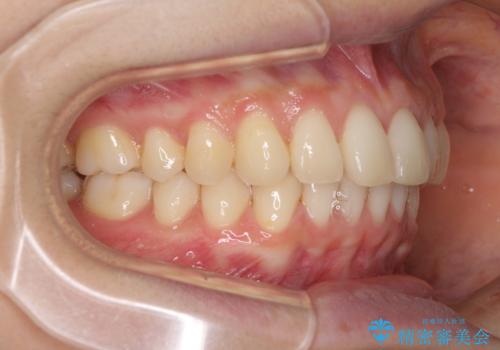

インビザラインによるディープバイトの改善

- 口元の前突感と深い咬み合わせ(ディープバイト)を気にして来院された患者様です。

インビザラインによる上下歯列の遠心移動(後方移動)と、それに伴う近心傾斜(前方傾斜)の改善により、口元の突出感とディープバイトを改善することとしました。

前歯のデコボコを最も気にしていましたが、咬み合わせが深く歯ぎしりが自由にできない点を指摘すると、常に食いしばってしまうことも悩みであることが分かりました。

咬合状態が大きく変化したため、治療後半では咬み合わせの位置が定まらなくなりました。上下の前歯に後戻り防止用のワイヤーを装着し、奥歯の咬合をフリーにしたことで1ヶ月ほどで咬み合わせが定まりました。